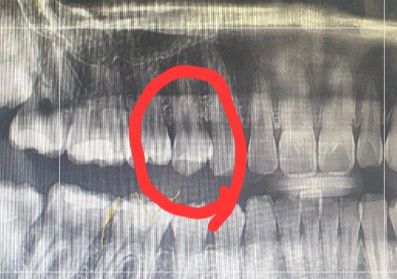

동그라미친 곳입니다 겉으로는 멀쩡해서 구분하기 어렵고 신경치료 해야하는 의견도 있고 신경치료말고 간단한 치료를 하라는 말도 있어서 의견 물어보기 위해 질문남깁니다

인접면 충치라 제거를 해봐야 알 수 있으나 사진상으로는 신경치료 가능성이 높아보입니다.

치아 뒷부분에 충치가 넓어 보이긴합니다. 조심히 제거해서 신경이 노출되지 않으면 신경치료를 안해도 되지만, 충치제거시 신경이 노출되면 신경치료를 해야될 가능성도 있습니다.

해당치아는 뒤쪽으로 충치가 있는것으로 보입니다

신경치료는 충치를 제가 하고 난 다음에 신경의감염여부에 따라 결정이 됩니다

신경치요의 가능성도 있지만 하지 않아도 될수 있습니다